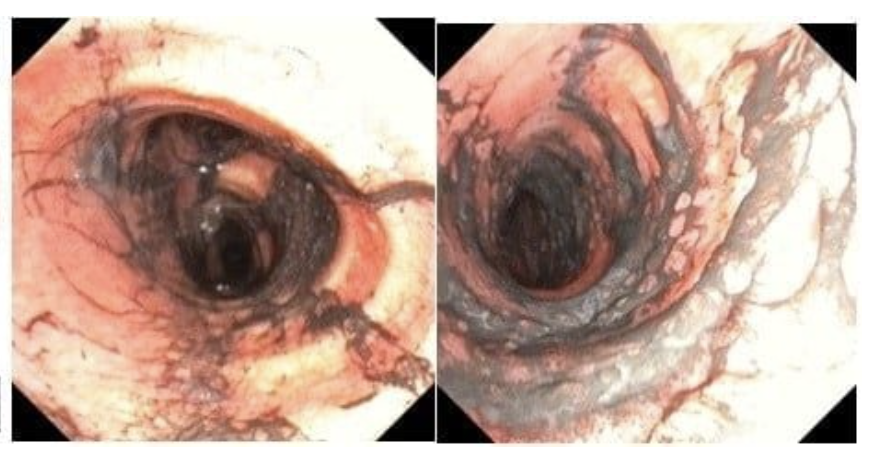

Đường thở của cả hai người bệnh bám nhiều bụi đen từ khói và tổn thương viêm sung huyết toàn bộ đường thở ghi nhận khi nội soi phế quản ống mềm tại giường

Chất tiết có rất nhiều muội than, tro bụi từ phổi của người bệnh được hút ra bằng phương pháp nội soi phế quản ống mềm tại giường

Nhận định nguy cơ cao tổn thương đường thở do hít phải tro bụi và muội than, các bác sĩ chuyên khoa hô hấp đã triển khai kỹ thuật nội soi phế quản ống mềm tại giường bệnh, kết hợp rửa phế quản ngay trong ngày nhập viện và duy trì nhiều ngày liên tiếp. Thủ thuật này giúp loại bỏ lượng lớn muội than, dịch tiết và chất độc trong đường thở, góp phần giảm viêm và cải thiện chức năng hô hấp.